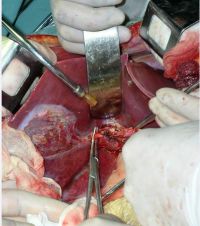

肝海绵状血管瘤手术切除

(1)充分显露肿瘤,一般作肋缘下斜切口,如果肿瘤位于右半肝,切口可自剑突沿右肋缘下至右第12肋;如果肿瘤位于左半肝,显露困难,则可以采用双肋缘下“人”字形切口,这样可充分显露肿瘤便于操作;对于需行右三叶切除的巨大肝血管瘤,必要时可作胸腹联合切口

(2)充分游离肝脏,在分离肿瘤和切肝前,可先结扎患侧肝动脉,使肿瘤缩小、变软,有利于手术操作。通常采用先在肝十二指肠韧带处放置一根橡皮管,以阻断入肝血流,更便于分离和切除肿瘤,且可防止手术过程中大出血。切肝前应仔细分离、切断和结扎肿瘤周围诸韧带及粘连组织,使肿瘤和患侧肝脏充分游离,游离的程度以达到术者可以用手握住肝切线并控制肝创面出血为原则。对于右肝巨大血管瘤已达肝后下腔静脉前壁者,充分游离右侧肝脏后,可以将肝脏向左侧翻转,仔细分离,暴露下腔静脉前壁的肝短静脉,逐根结扎,以免切肝时撕破下腔静脉壁或拉断肝短静脉。

(3)切肝应在常温下阻断肝门后进行,每次阻断时间为15~20min,如1次阻断未能切下,放松3~5min后,再行第2次阻断,直至把肿瘤切下为止;如果有可能,可以选择性地阻断患侧肝脏的肝门,这样可以延长阻断时间。

(4)肝切线的选择,肝切线应选在偏向或靠近正常肝组织处,用血管钳边钳夹、边切断结扎所有断面血管和胆管。直至肿瘤完全切除。多发性血管瘤或血管瘤病变广泛,需作局部或主瘤切除者,应注意切线尽量靠近正常肝组织,不然易引起大出血;切忌在瘤体上切割或缝扎,以免造成渗血不止;待主瘤切除后,小的血管瘤可用捆扎法处理。

(5)肿瘤切除后,应对肝创面进行彻底止血,活动性出血可以行“8”字缝合,无明显出血后,可用一片游离大网膜覆盖肝创面并缝合固定,也可用对拢缝合肝创面。后腹膜粗糙面予以缝合止血,膈下置双套管持续负压吸引

(6)对巨大肝海绵状血管瘤切除时,术前还应从颈外静脉颈内静脉或大隐静脉放置中心静脉导管右心房附近,供输液输血或术中测量中心静脉压用。因瘤体可压迫下腔静脉,造成静脉回流不畅,故全部输液输血应在上肢进行,并常规显露一侧桡动脉,以便在大出血时作紧急动脉输血用,以利提高手术安全性。